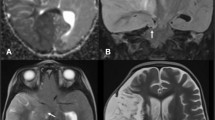

Case

A patient in the fourth decade of life with no significant medical history was found down with global aphasia, right-sided hemiplegia, and homonymous hemianopsia. The patient had been seen normally 36 h prior. Initial non-contrast computed tomography (CT) revealed an established left middle cerebral artery territory infarction (Fig. 1B–C). The left internal carotid (ICA) and middle cerebral arteries (MCA) were occluded, as evidenced by the hyperdense arteries (arrows in Fig. 1A). A CT angiogram revealed an ICA dissection with thrombus propagation into the ipsilateral MCA (image not shown). Over the next 24 h, the patient developed progressive somnolence. A repeat CT head showed an evolving MCA infarct with increasing mass effect over the ipsilateral ventricular system (Fig. 1D–F). The following day, the patient’s level of consciousness further deteriorated, requiring sustained noxious stimulation to achieve eye-opening. A new CT head (Fig. 1G–I) showed increased cerebral edema and worsening mass effect, with a rightward midline shift of 11 mm. This was associated with marked compression of the left lateral ventricle and third ventricle. There were signs of early hydrocephalus with mild enlargement of the right temporal horn (Arrows in Fig. 1G and H). The patient was intubated, received a bolus of 23% hypertonic saline, and was emergently taken to the operating room for decompressive hemicraniectomy with no complications. A postoperative CT head showed appropriate cerebral decompression with a slightly improved midline shift. (Fig. 2A) The next day, the patient’s mental status improved significantly. Seven days later, he was discharged to inpatient rehabilitation, and home 1 month after. On discharge, the patient required assistance for transfers and bodily needs but could stand with help for 40 s (modified Rankin scale [mRS] 4). Severe hemiparesis, aphasia, and right homonymous hemianopia persisted. The patient continued to improve with outpatient rehabilitation and underwent cranioplasty without complications (Fig. 2B). One year after surgery, the patient could walk up to 4 blocks without assistance and communicate with others despite severe expressive aphasia (mRS 2). Unfortunately, the patient developed medically refractory epilepsy with numerous hospitalizations and severe spasticity requiring regular botulinum toxin injections.

Evolution of malignant MCA infarction. A–C Initial non-contrast CT scan. Arrows in A show the hyperdense ICA and MCA signs, suggesting acute arterial occlusion. D–F Non-contrast CT scan at 24 h. G–I Non-contrast CT scan at 48 h. Arrows in G and H point to the dilated temporal horn of the right lateral ventricle.